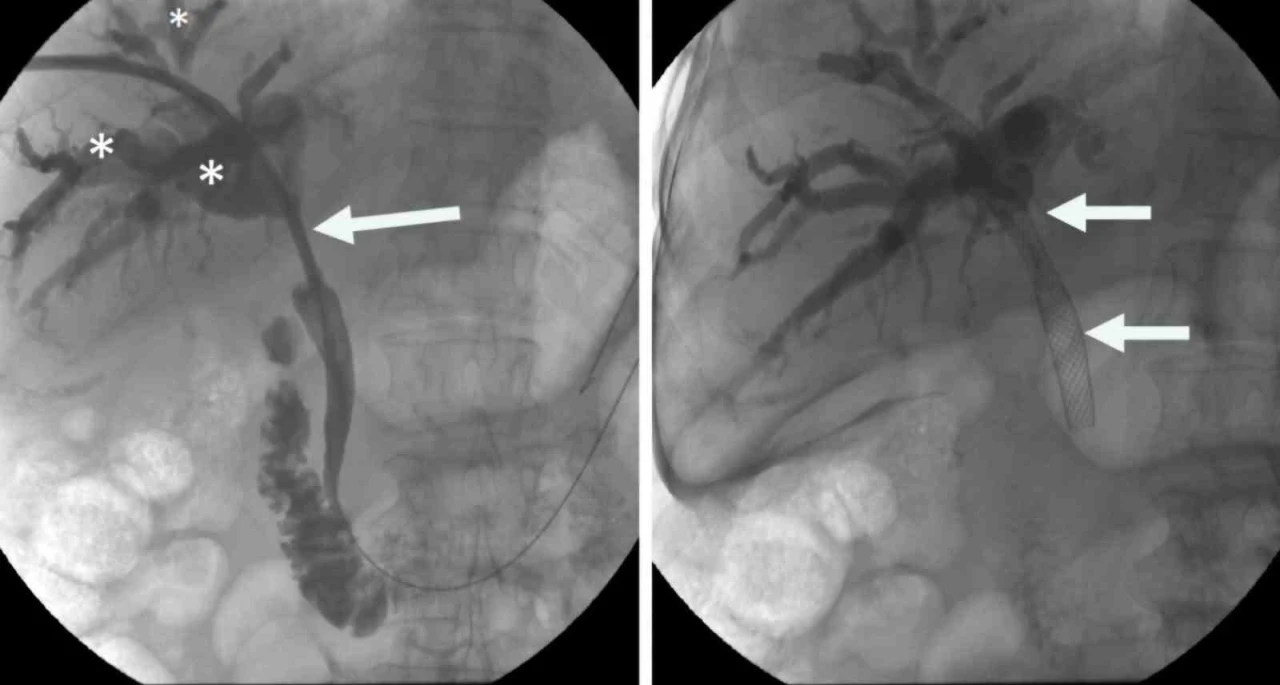

İzmir Ekonomi Üniversitesi Medical Point Hastanesi Tıbbi Direktör Ahmet Memiş’in öncülüğünde, farklı tıp disiplinlerinin işbirliğiyle geliştirilen hibrit yaklaşımlar, endoskopik, gastro ve girişimsel radyoloji teknikleri bir araya getirerek karmaşık safra yolu sorunlarında çığır açıyor. Bu yenilikçi yöntemler, hastaların iyileşme süreçlerini hızlandırırken, daha az travmatik operasyonlarla tedavi imkanı sunuyor.

Prof. Dr. Ahmet Memiş’in önderliğinde uygulanan bu yenilikçi yöntem, endoskopik teknikleri ve iğne ile giriş yöntemlerini tek bir operasyonda birleştiriyor. Bu sayede, daha önce tedavisi çok zorlu kabul edilen karmaşık safra yolu problemleri artık daha etkili ve minimal invaziv bir şekilde tedavi edilebiliyor. Hibrit yaklaşımların en önemli avantajlarından biri, hastaların bedenine minimum düzeyde zarar vermesidir. Büyük cerrahi kesilerin yerine, endoskopik, gastro ve girişimsel radyoloji yöntemler kullanılarak, iğne deliği kadar küçük girişimlerle operasyonlar gerçekleştiriliyor. Bu da hastaların ameliyat sonrası ağrılarını azaltıyor, enfeksiyon riskini düşürüyor ve hastanede kalış sürelerini kısaltıyor. ‘Hibrit yaklaşım’

Prof. Dr. Ahmet Memiş, “Hibrit yaklaşım, sadece tedavi değil, aynı zamanda tanı sürecinde de önemli avantajlar sunuyor. Hekim, hastanın vücuduna dokunmadan, radyolojik görüntüleme teknikleriyle hastalıklar daha hızlı ve doğru bir şekilde tespit ediliyor. Bu da tedavi sürecinin daha etkin bir şekilde planlanmasına imkan sağlıyor. Farklı disiplinlerden uzman hekimlerin bir araya gelerek oluşturduğu sinerji, karmaşık safra yolu sorunlarında başarı oranını önemli ölçüde artırıyor. Bu sayede, hastalar daha hızlı iyileşme göstererek günlük yaşamlarına daha kısa sürede dönebiliyor. Geleneksel cerrahi yöntemlerde uzun iyileşme süreleri ve yoğun ağrılar yaşanırken, minimal invaziv yaklaşımlar sayesinde bu sorunlar ortadan kalkıyor. Hastalar, operasyon sonrası çok daha kısa sürede taburcu oluyor ve gündelik aktivitelerine hızla dönebiliyorlar. Bu da hem hasta konforunu artırıyor hem de sağlık sisteminin üzerindeki yükü hafifletiyor” dedi.